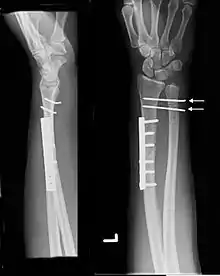

Galeazzi fracture after surgical fixation

Galeazzi fractures are best treated with open reduction of the radius and the distal radio-ulnar joint.[3] It has been called the "fracture of necessity," because it necessitates open surgical treatment in the adult.[4] Nonsurgical treatment results in persistent or recurrent dislocations of the distal ulna.[1] However, in skeletally immature patients such as children, the fracture is typically treated with closed reduction.[1]